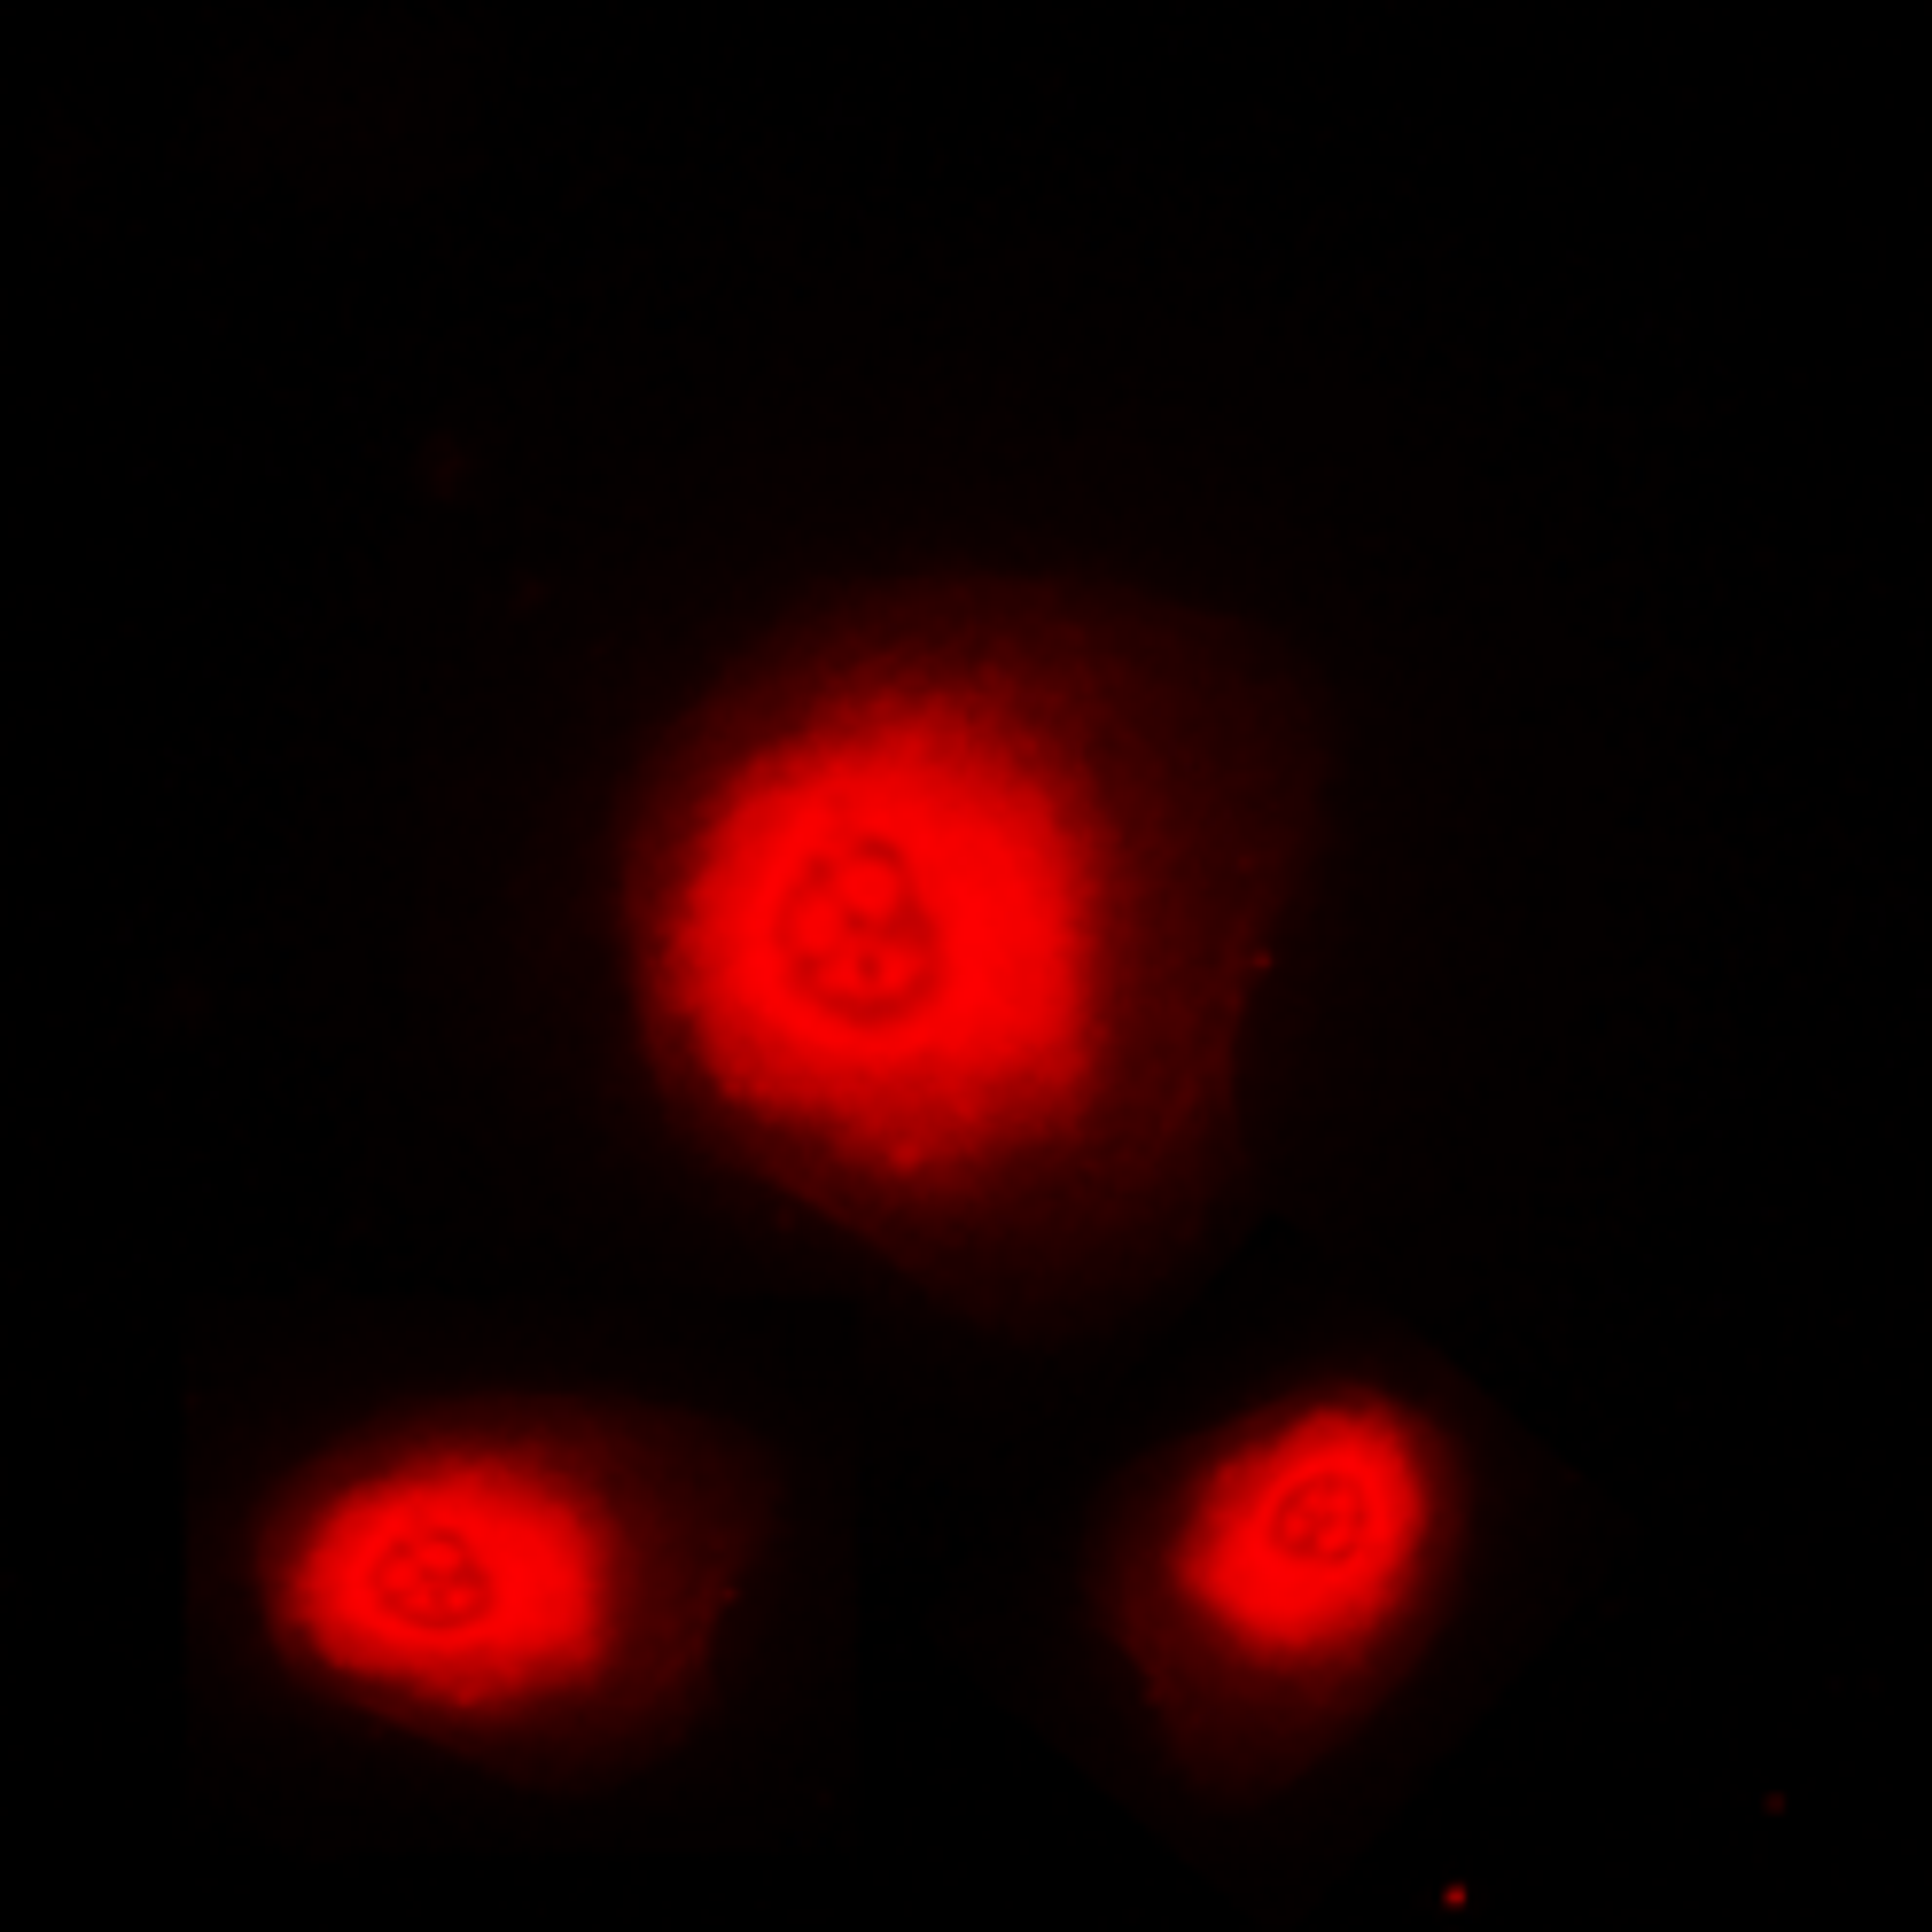

Estrogen Receptor beta antibody

- orb389114

- Host

- Mouse

- Reactivity

- Horse (Equine), Human, Monkey, Pig (Swine), Rat

- Applications

- Flow Cytometry, Immunofluorescence (Paraffin-Embedded Sections), Immunohistochemistry (Paraffin-Embedded Sections), Western Blotting